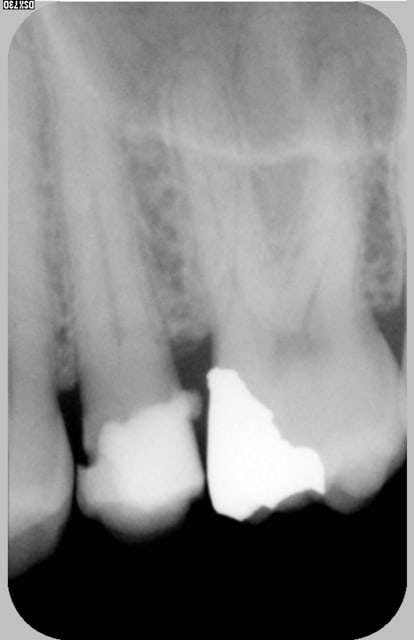

Bonjour je cherche un endo qui travaille sous microscope dans la région de Lille ou Paris pour traiter cette dent qui a besoin d'être couronner

les Rx, c'est l'etat actuel de la dent? ou c'est avant que tu ouvres et cherche à trouver les canaux?

pas possible il ne reste plus qu'une coquille d'émail car cette dent a eu un composite pendant longtemps et je ne suis pas sûre qu'elle soit vivante .(changement de teinte, aucune sensibilité au froid)